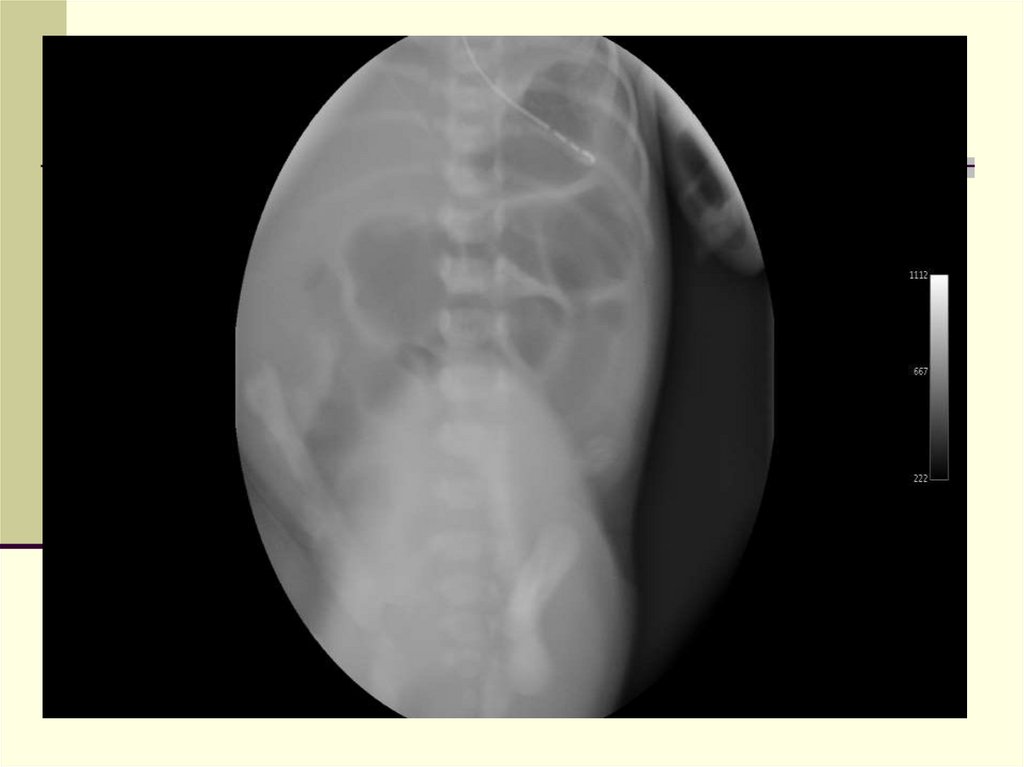

26. Диагноз

Обзорная рентгенография

Несколько расширенных петель с округлыми

образованиями в просвете

Отсутствие уровней

Кальцинаты в брюшной полости

Ирригография

27. Консервативное лечение неосложненного мекониевого илеуса

4) Контрастная клизма с гастрографином или урографином

(гиперосмолярный раствор)

NB! Контроль диуреза и состояния гемодинамики (угроза развития

NB! Клизма с контрастом может быть повторена через12 – 24 часа

NB! Контраст должен проходить в расширенные петли кишечника